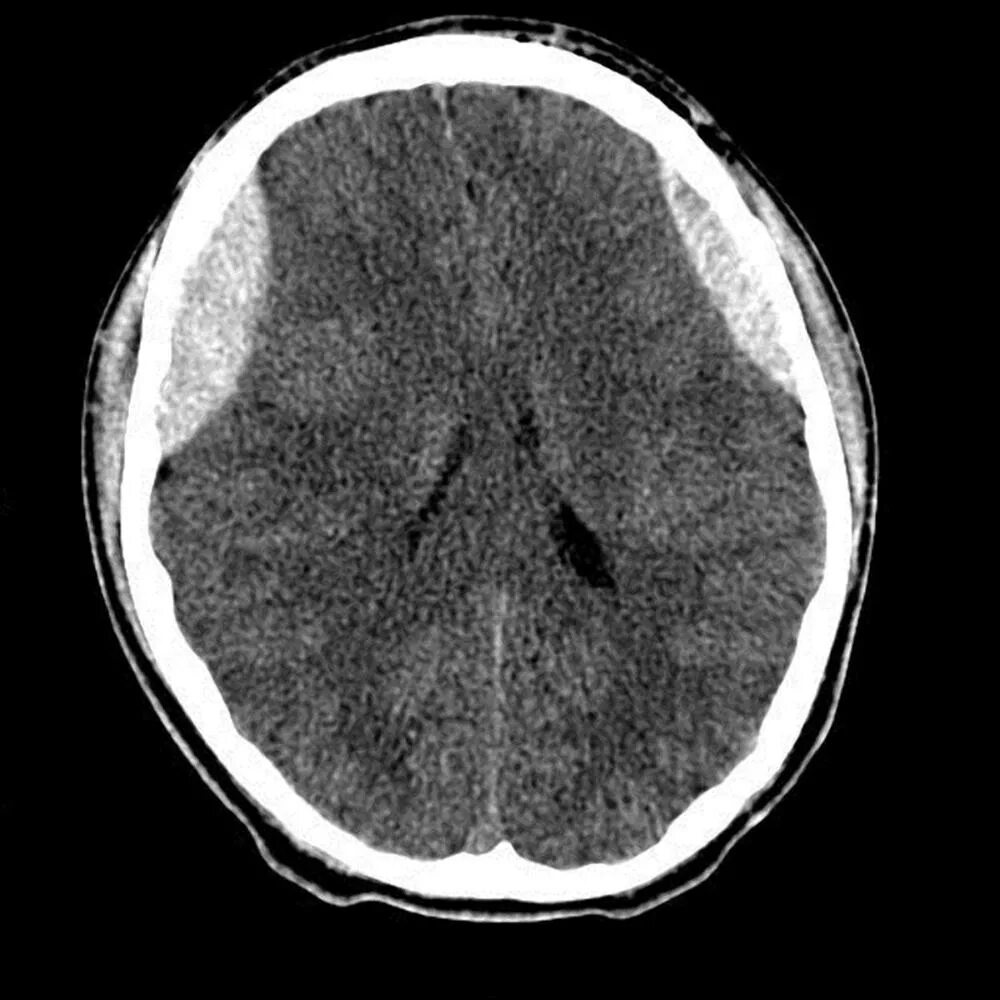

Ушиб мозга на кт